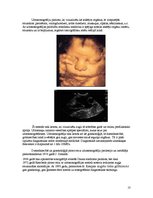

augļa ultrasonogrāfiskā izmeklēšana - precizējot grūtniecības laiku, norisi, kontrolējot augļa veselības stāvokli, diagnosticējot iespējamās iedzimtās patoloģijas, nabas saites stāvokli, placentas novietojumu un gatavības pakāpi, regulāri novērojot arī mātes slimības (ja tādas pastāv).